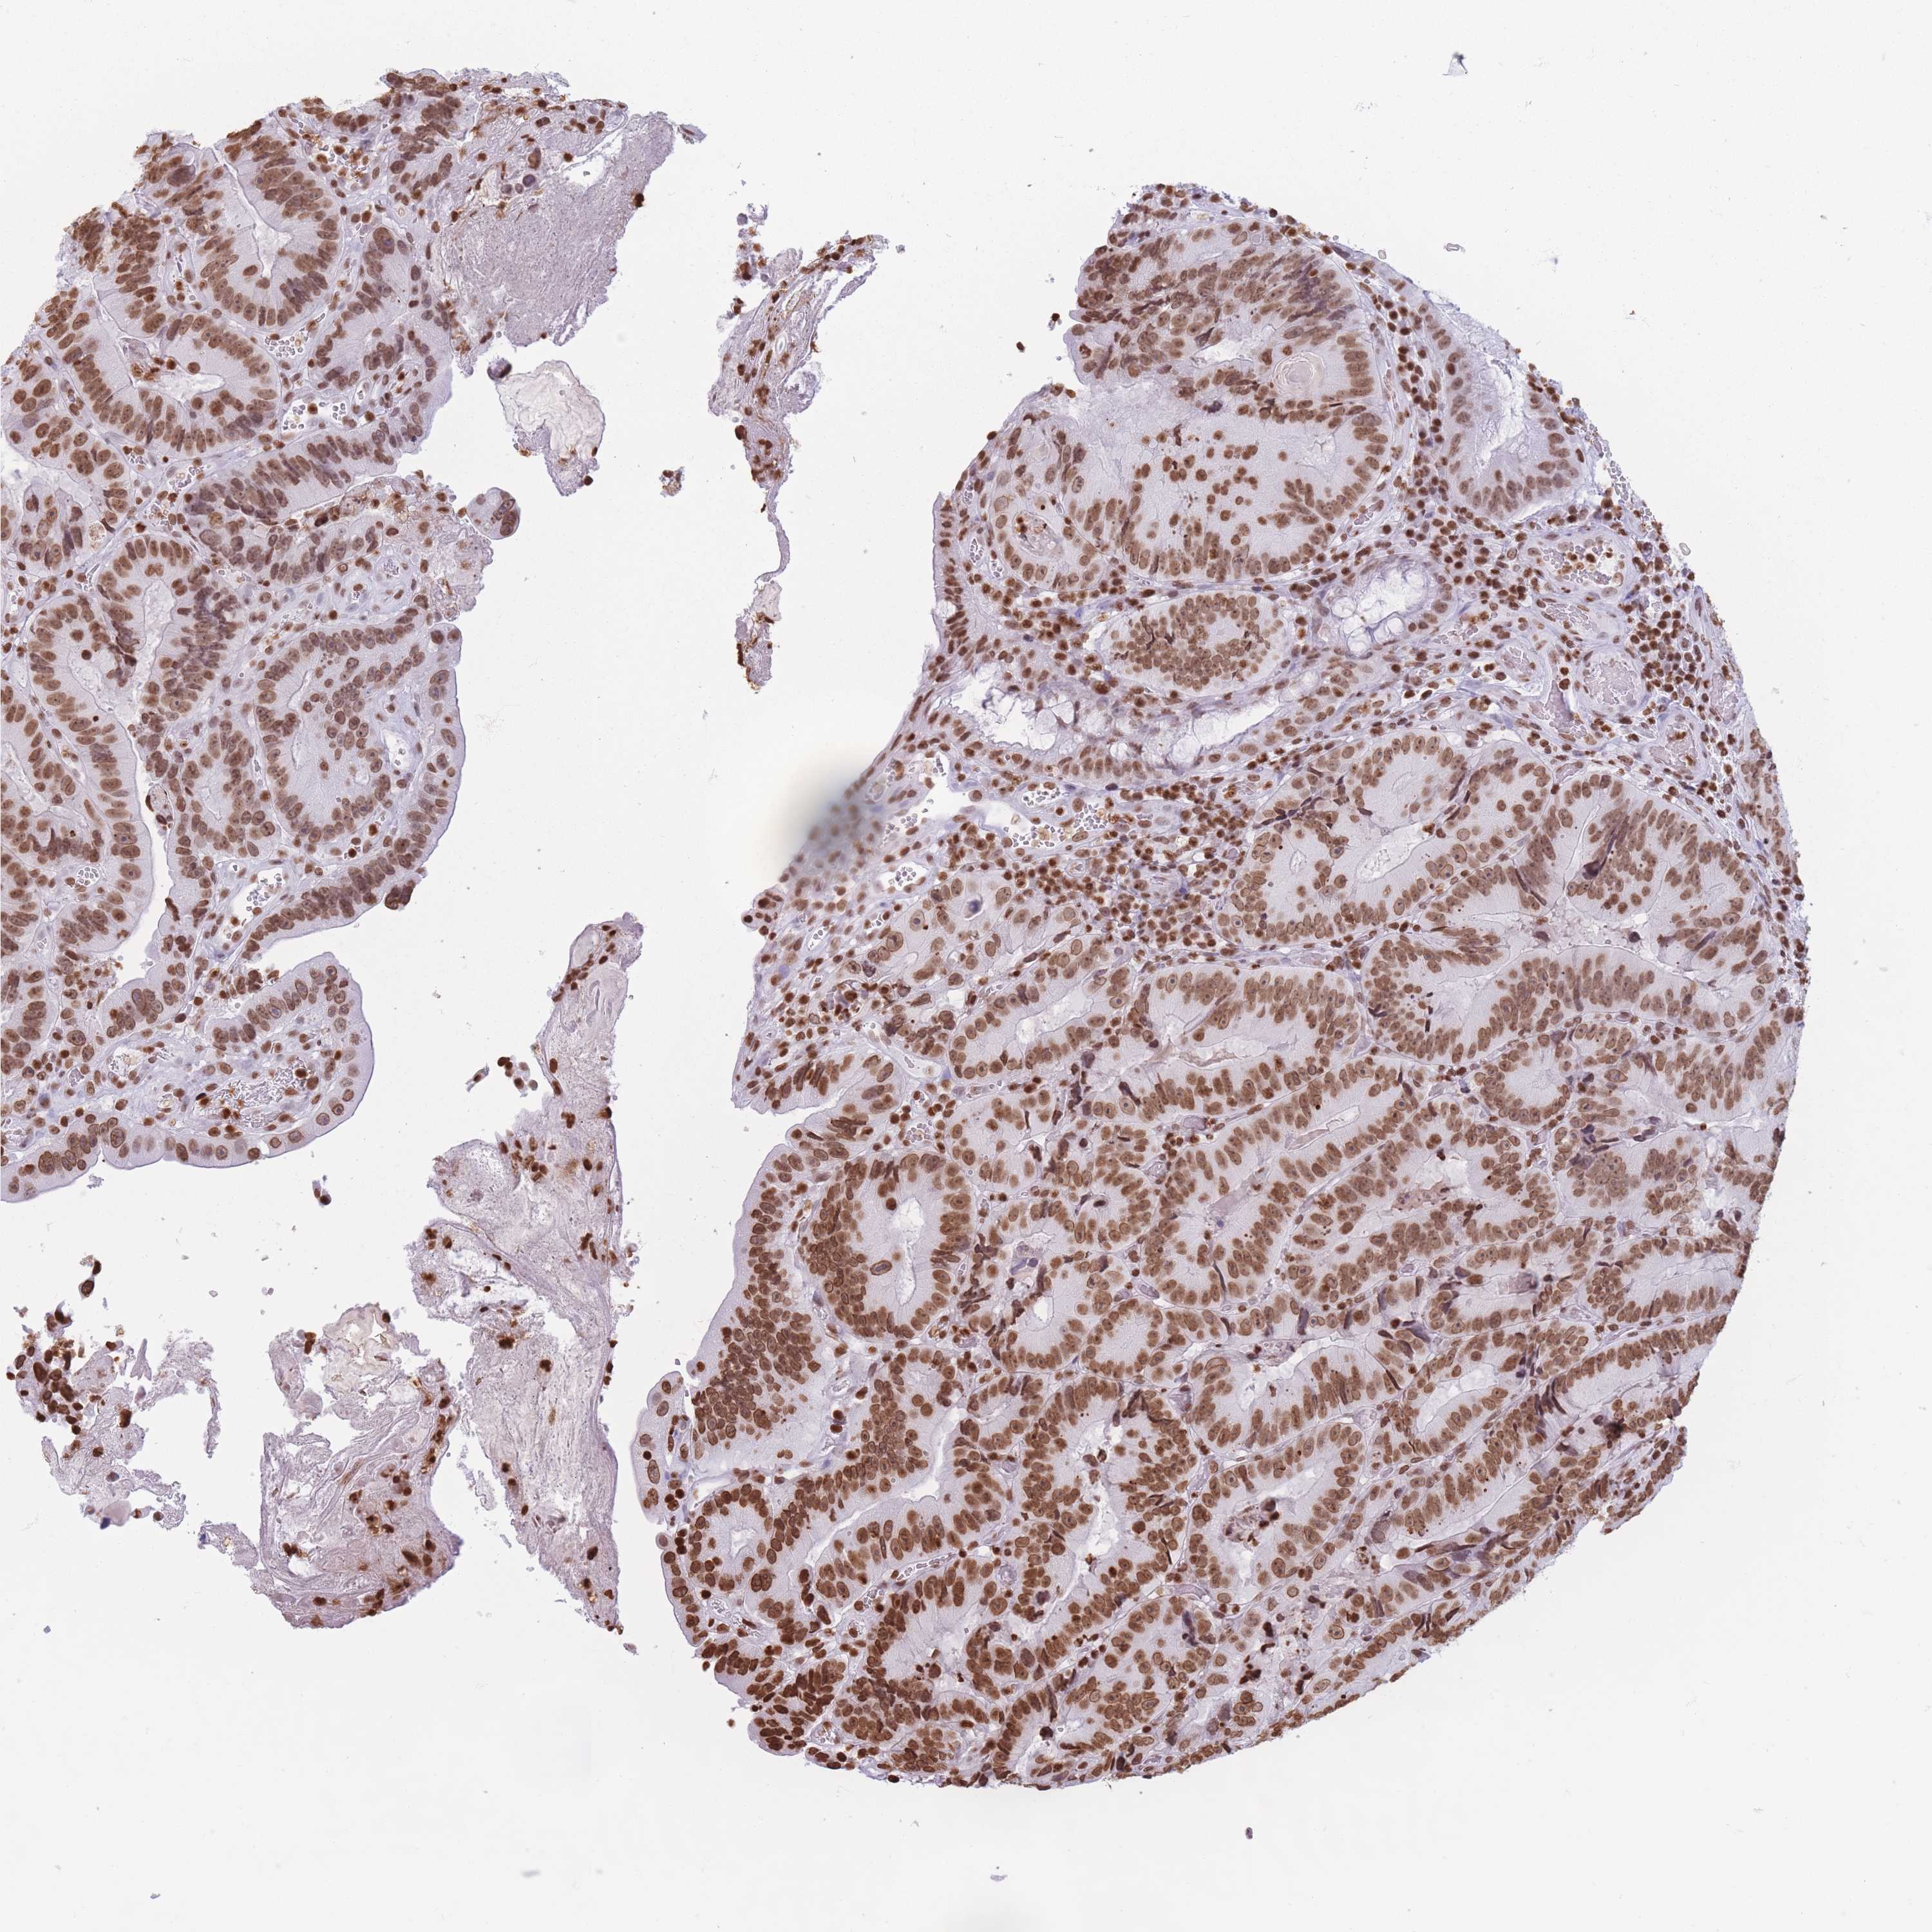

CANCER COLORECTAL CANCER Show tissue menu

Colorectal cancer

Human cancer

Colon adenocarcinoma

Rectum adenocarcinoma